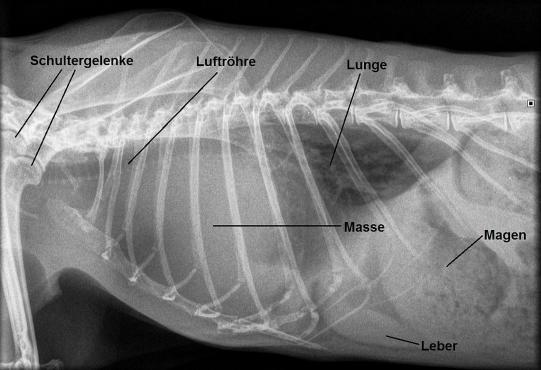

Da dieser beidseitig aufgetretene Exophtalmus nicht schlüssig erklärt werden kann, wird die Nagermedizin-Literatur konsultiert. In zwei Standartwerken ist das Problem nicht erwähnt, erst eine Internetrecherche weckt den Verdacht, dass das Problem durch einen Bluthochdruck bedingt sein könnte, welcher den Exophtalmos bewirken kann. Ein Bruströntgen zeigt denn auch einen grossen Schatten, welcher entweder durch ein stark vergrössertes Herz oder aber einen Tumor im Brustkorb hervorgerufen sein könnte. Ein Ultraschall zeigt dann, dass es sich beim Schatten tatsächlich um eine grosse Geschwulst handelt, welche im vorderen Teil des Brustkorbes entspringt, die Lunge verdrängt und auch etwas Flüssigkeitsbildung zwischen Lunge und Brustkorb (Pleuraerguss) provoziert hat. Trotz der starken Verkleinerung des Lungenvolumens zeigt das Tier aber keine Atemnot.